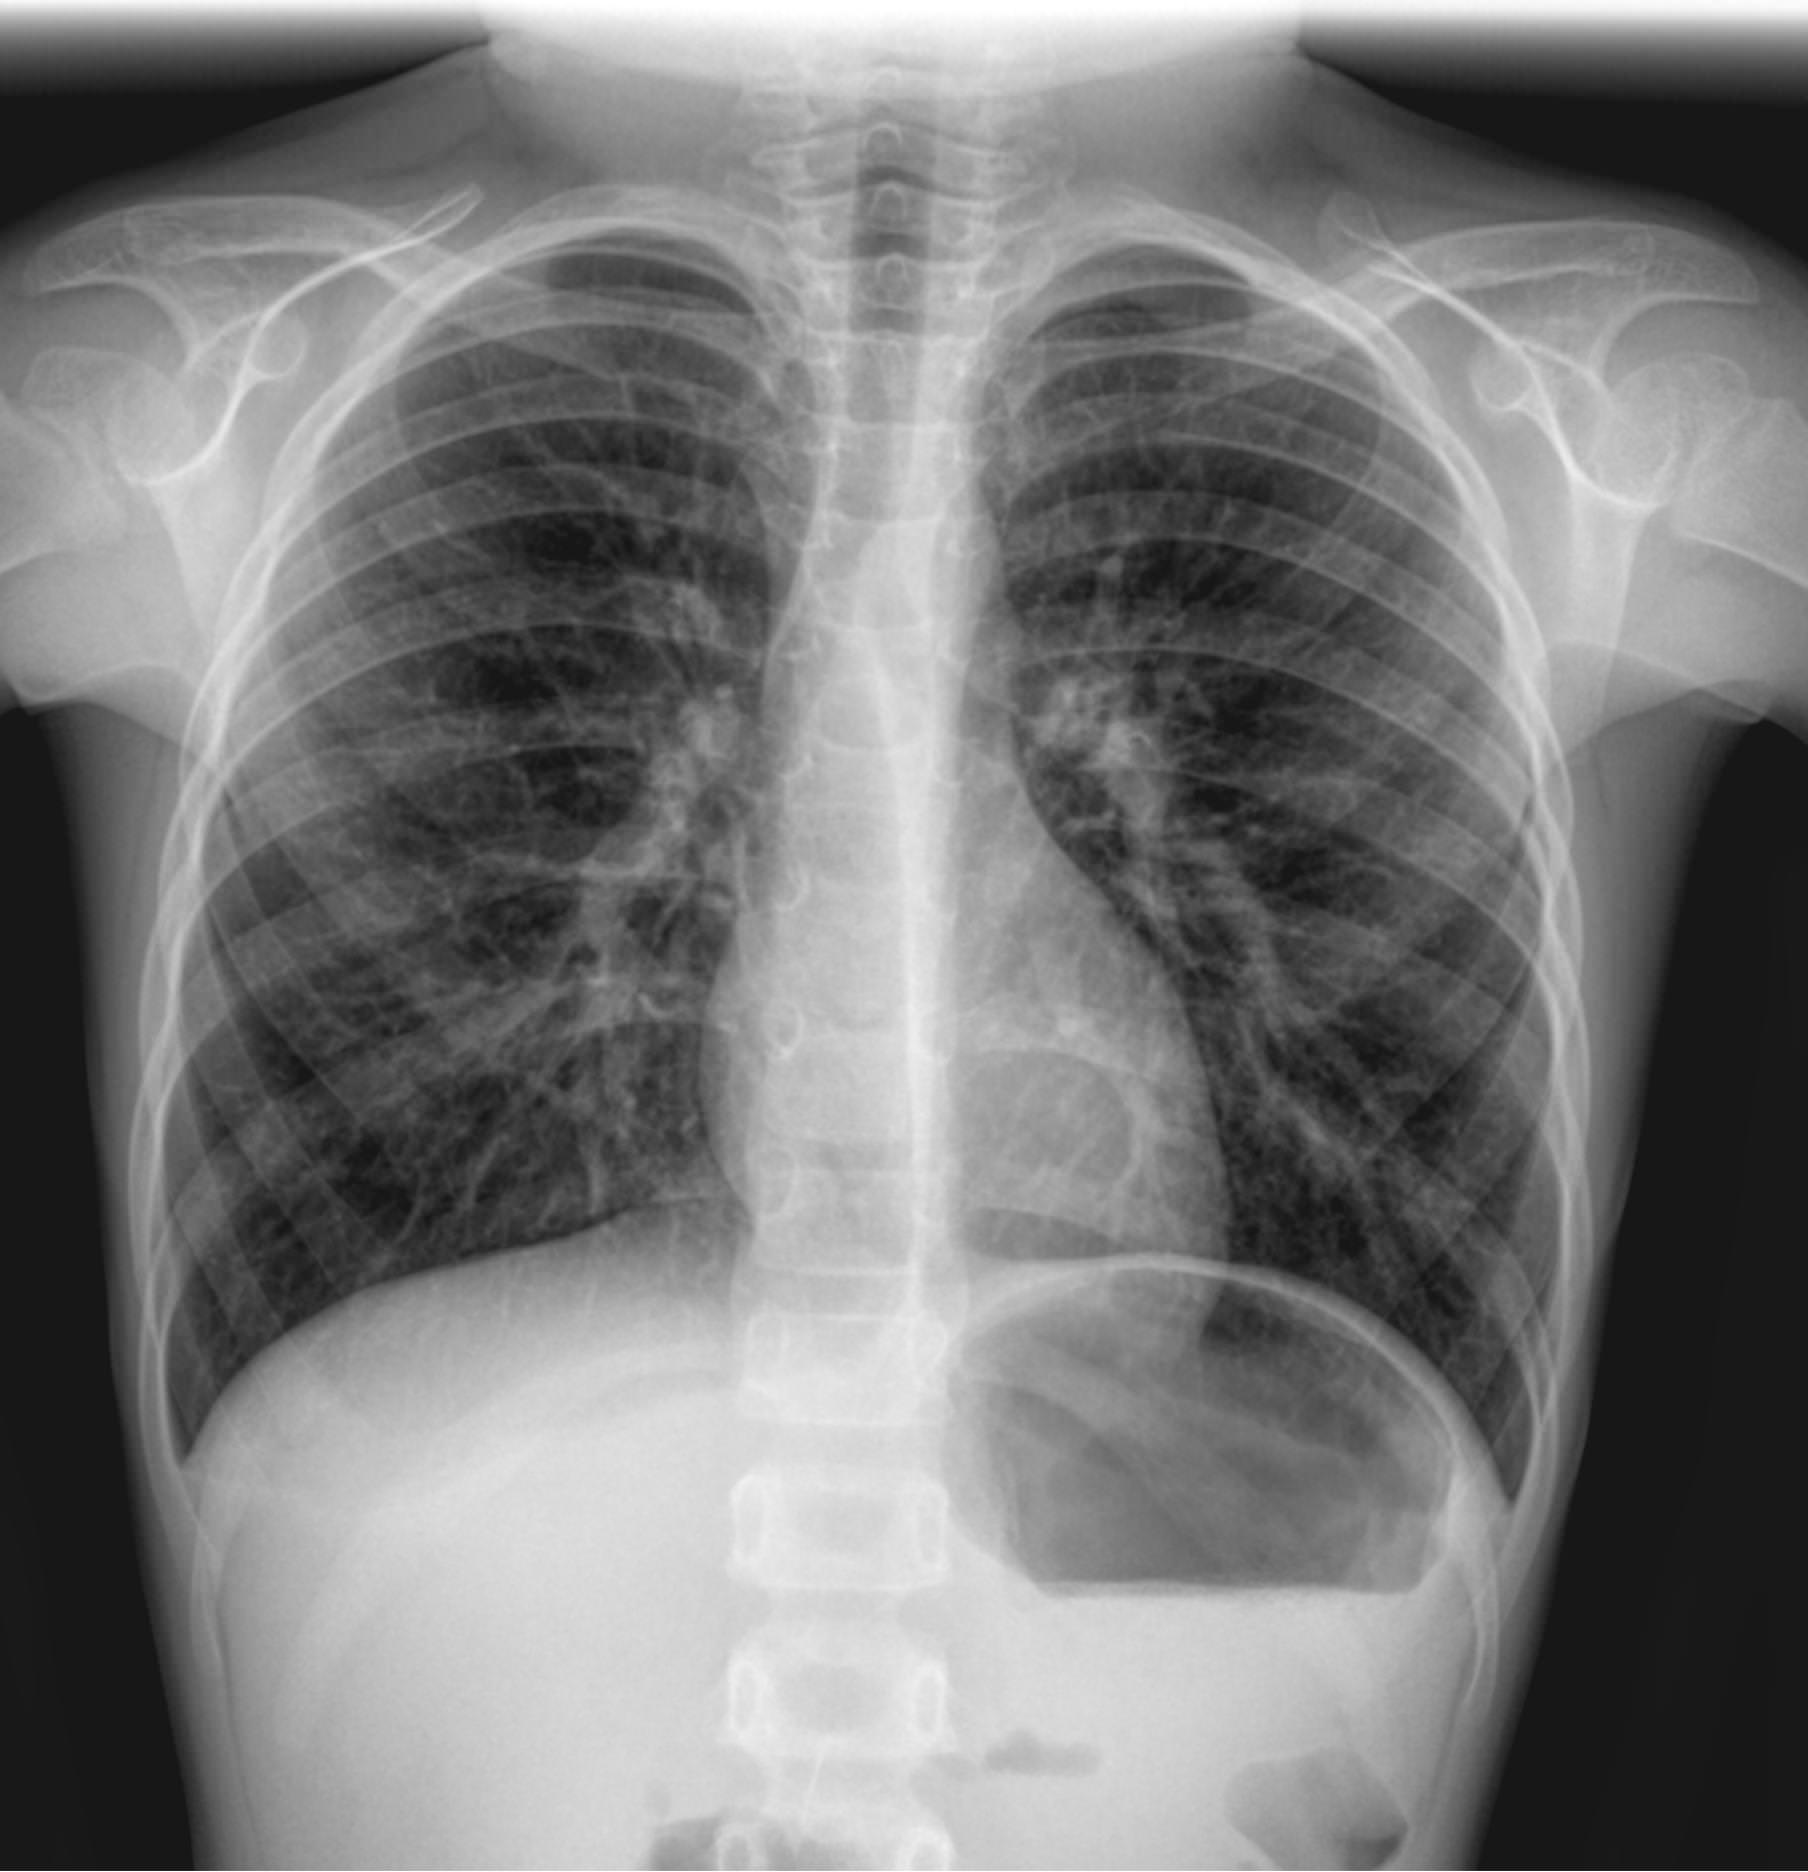

Диагностика с помощью рентгеновского излучения основана на его способности проходить сквозь живые и неживые объекты. В том числе, через тело человека. Органы разной плотности поглощают разное количество излучения, в результате на классическом негативном снимке наиболее плотные образования, кости, отображаются самыми светлыми, а наполненные воздухом ― почти черными. Мягкие ткани визуализируются как пятна серых оттенков. Участки, цвет и форма которых не типичны, говорят о патологии.

Снимок грудной клетки используют, чтобы получить изображение расположенных здесь органов: легких и дыхательных путей, контуров сердца с сосудами, а также позвоночника и костей. Обычно для диагноза достаточно одного снимка ― в прямой проекции, когда лучи идут сзади наперед. Иногда врач назначает снимок в боковой проекции, то есть слева или справа. Это необходимо, если требуется более точно определить сегмент поражения или достоверно исключить патологический процесс. Крайне редко требуются косые проекции, но они тоже бывают.

Что показывает рентген грудной клетки

На рентгенограмме видны следующие образования, расположенные в грудной клетке:

• Мягкие ткани: грудные мышцы, кожные складки;

• Костный скелет: ребра, ключицы, грудина, нечетко ― позвонки, в пожилом возрасте ― хрящи;

• Легочные поля: определяются их прозрачность, симметричность, легочный рисунок;

• Корни легких: топография, форма, структура, ширина;

• Средостение: положение сердца и сосудов, формирующих его дуги;

• Купол диафрагмы: четкость, местонахождение;

• Синусы: свободные или заполненные.